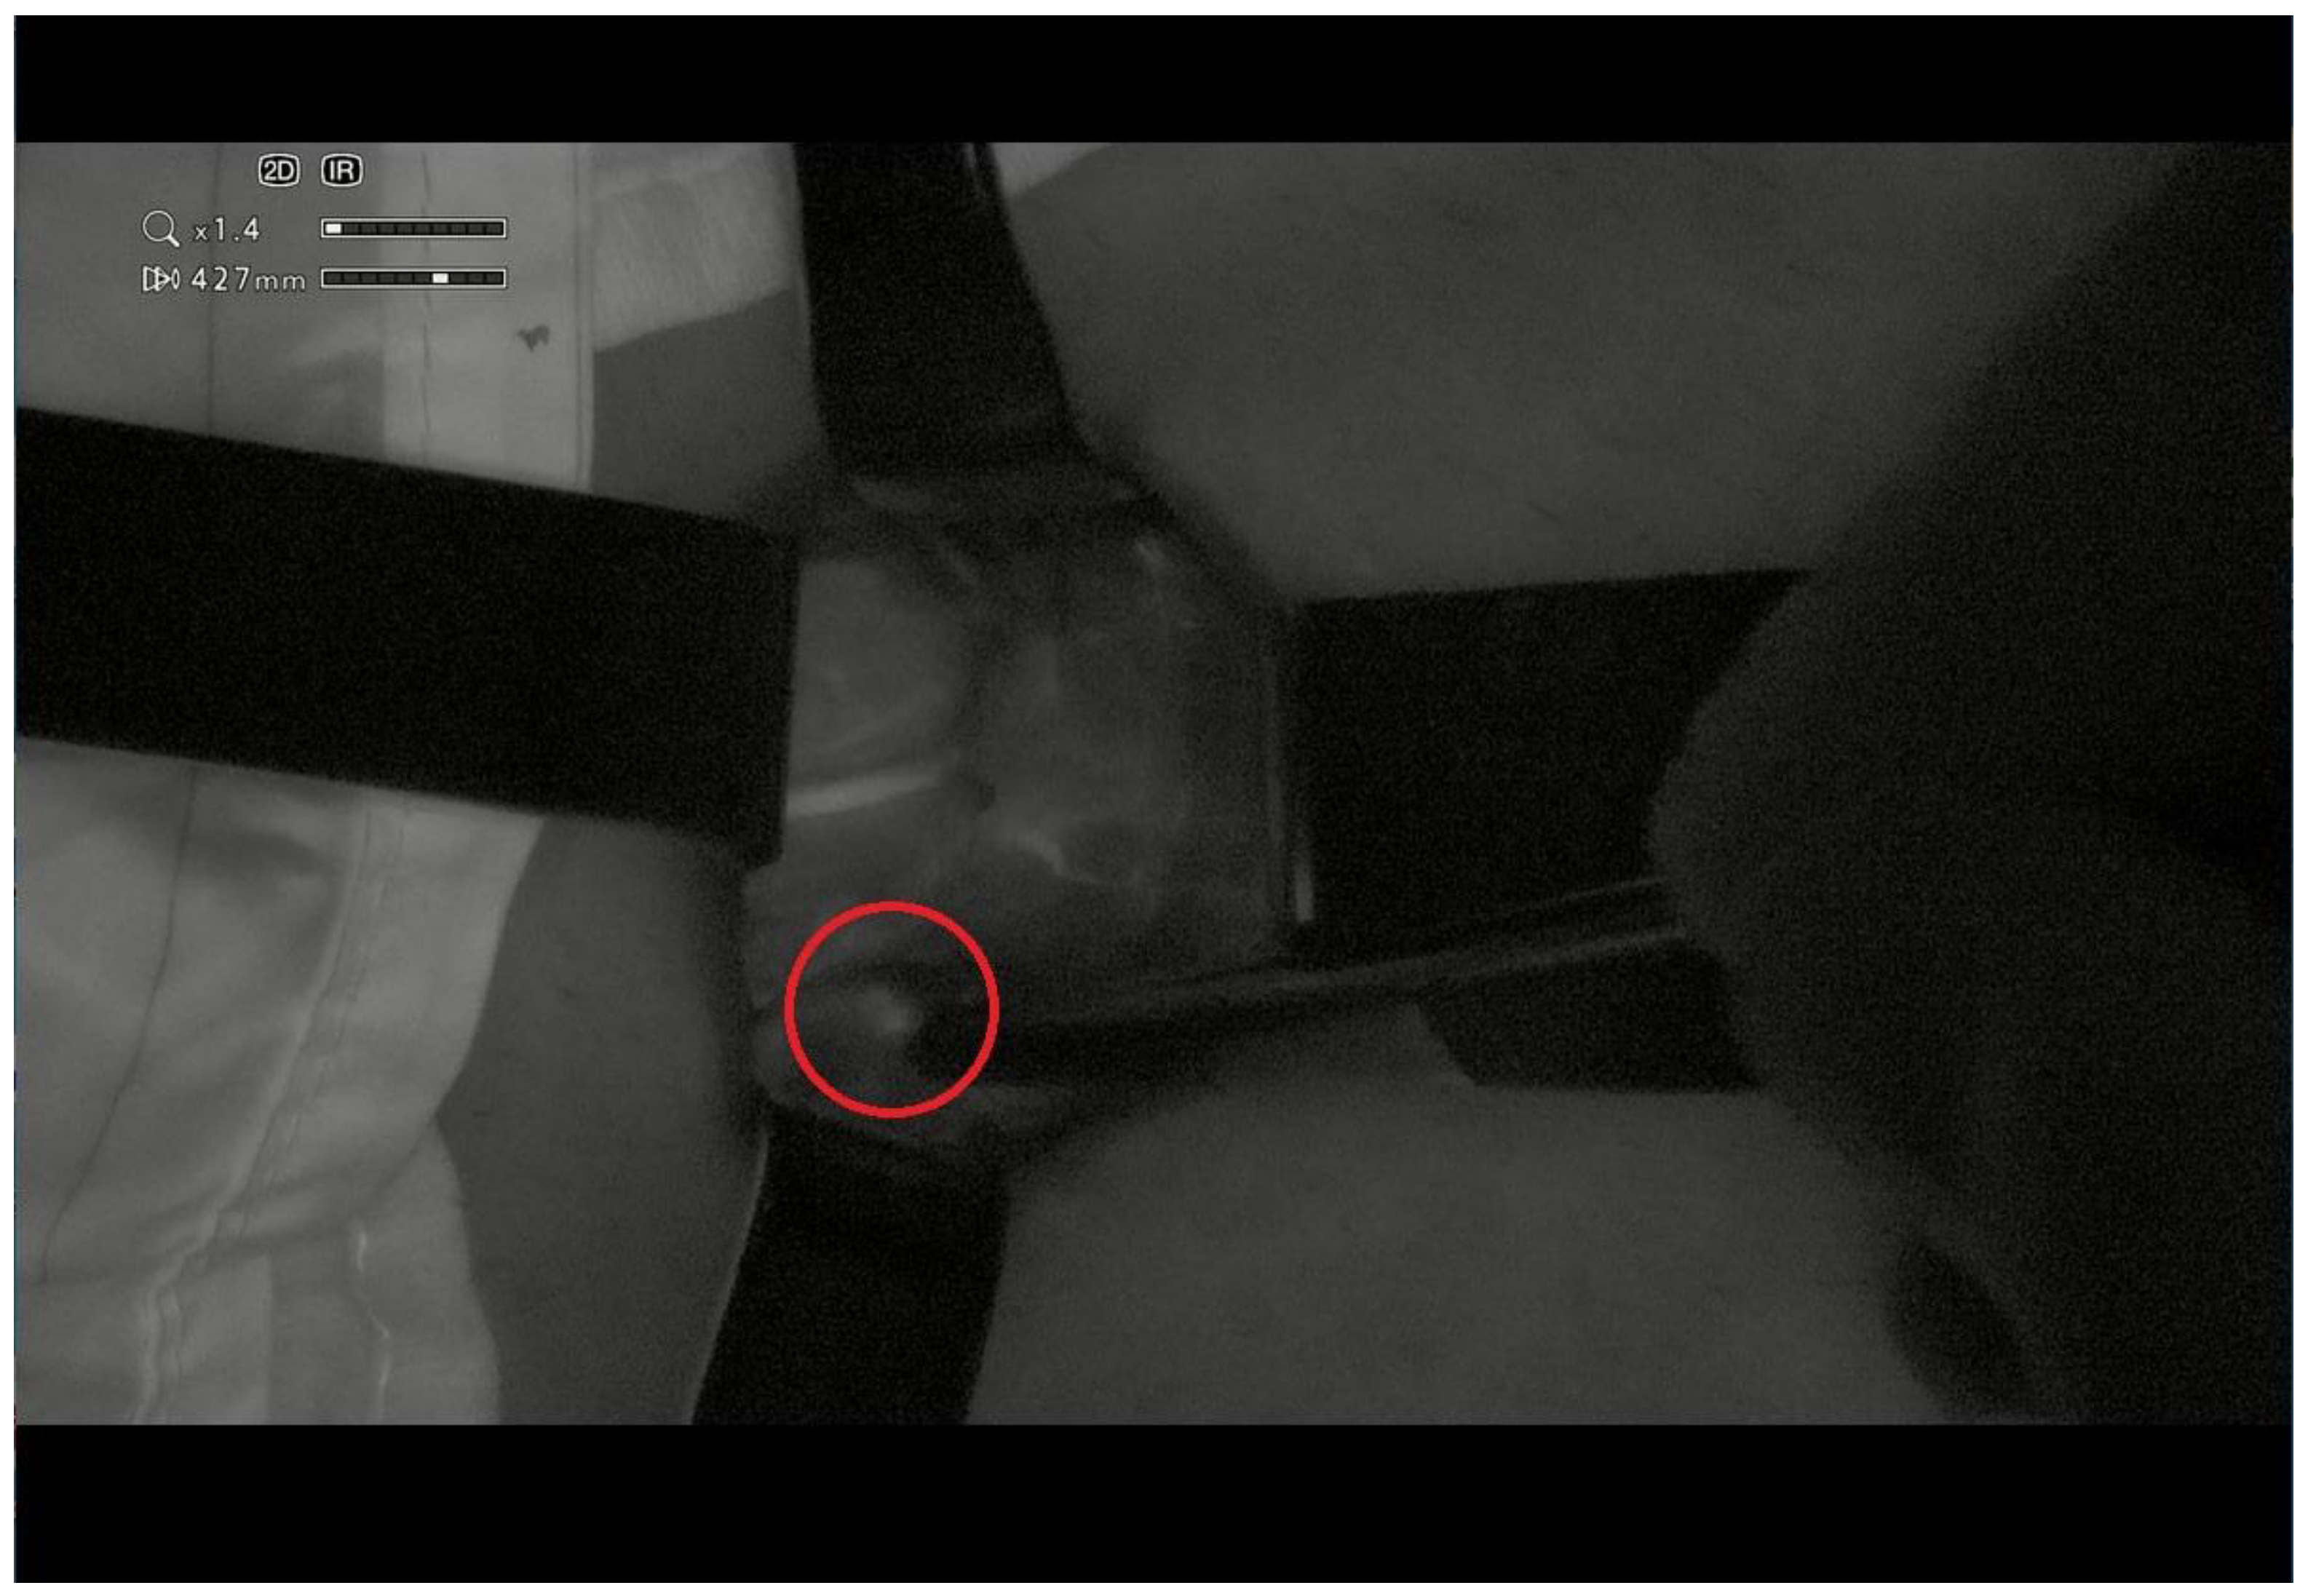

First Application of the Orbeye™ 4K 3D Exoscope in Recurrent Papillary Thyroid Cancer Surgery

2. Case Presentation